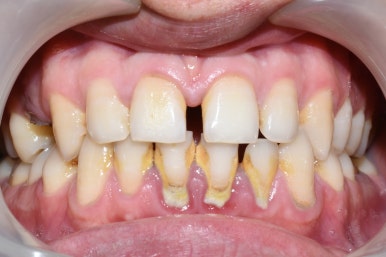

치석과 착색이 있는 치아

위와 같이 치석이 계속 쌓여 잇몸뼈를 녹이게 된다면

스케일링 전 , 후/ 시청역 연세예감치과

스케일링 전 후